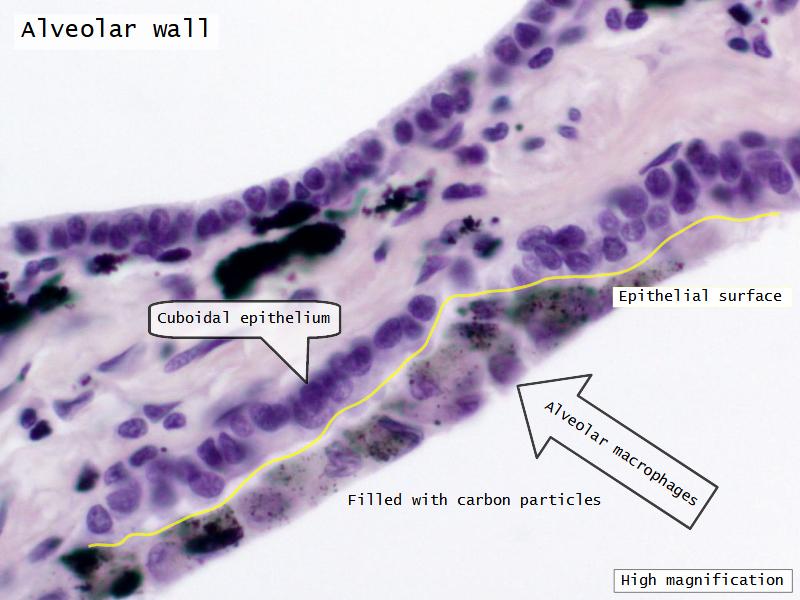

What cells are present?

Components of the Blood-Air Barrier?

- Respiratory bronchioles

- Conducting -> Respiratory

- Simple cuboidal epithelium

- Secretory cells

- Alveoli